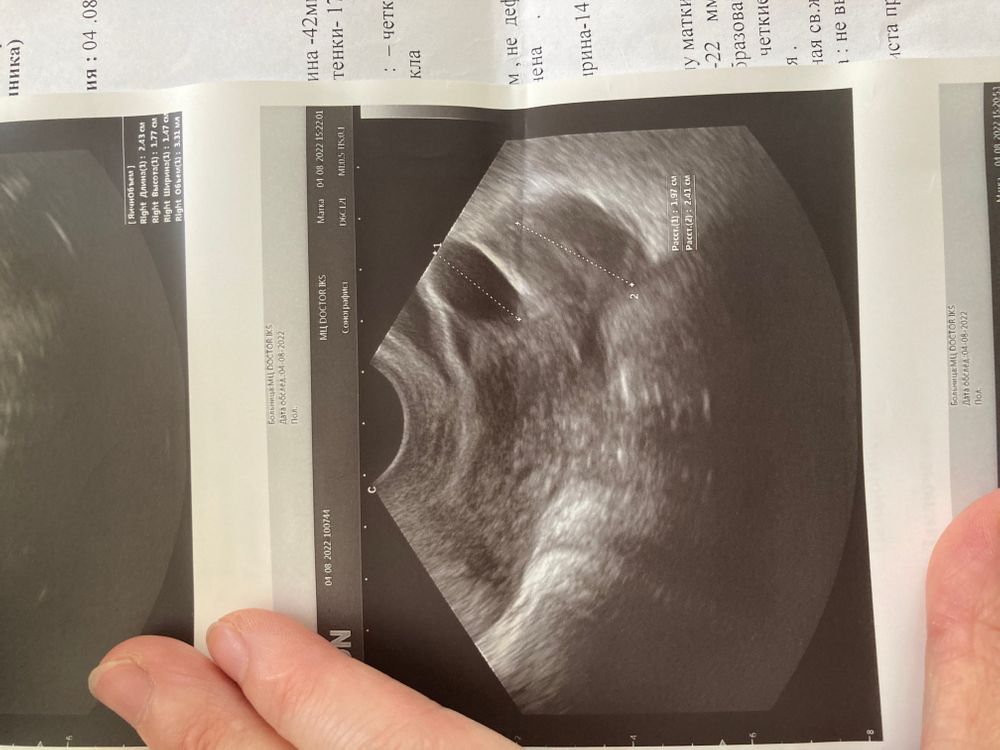

Что это?узи фолликулометрия

Доминантный фолликул ?Желтое. Тело?или Киста ?есть малое количество жидкости позади матки еще(незначительное)

Это фолликул. Какой размер намерили? Это точно не Желтое тело тк желтое тело с перегородками

Ну пока просто нелопнувший фолликул , будет размером ближе к 30 и без перспективы к овуляции то будет киста , на жт не похоже